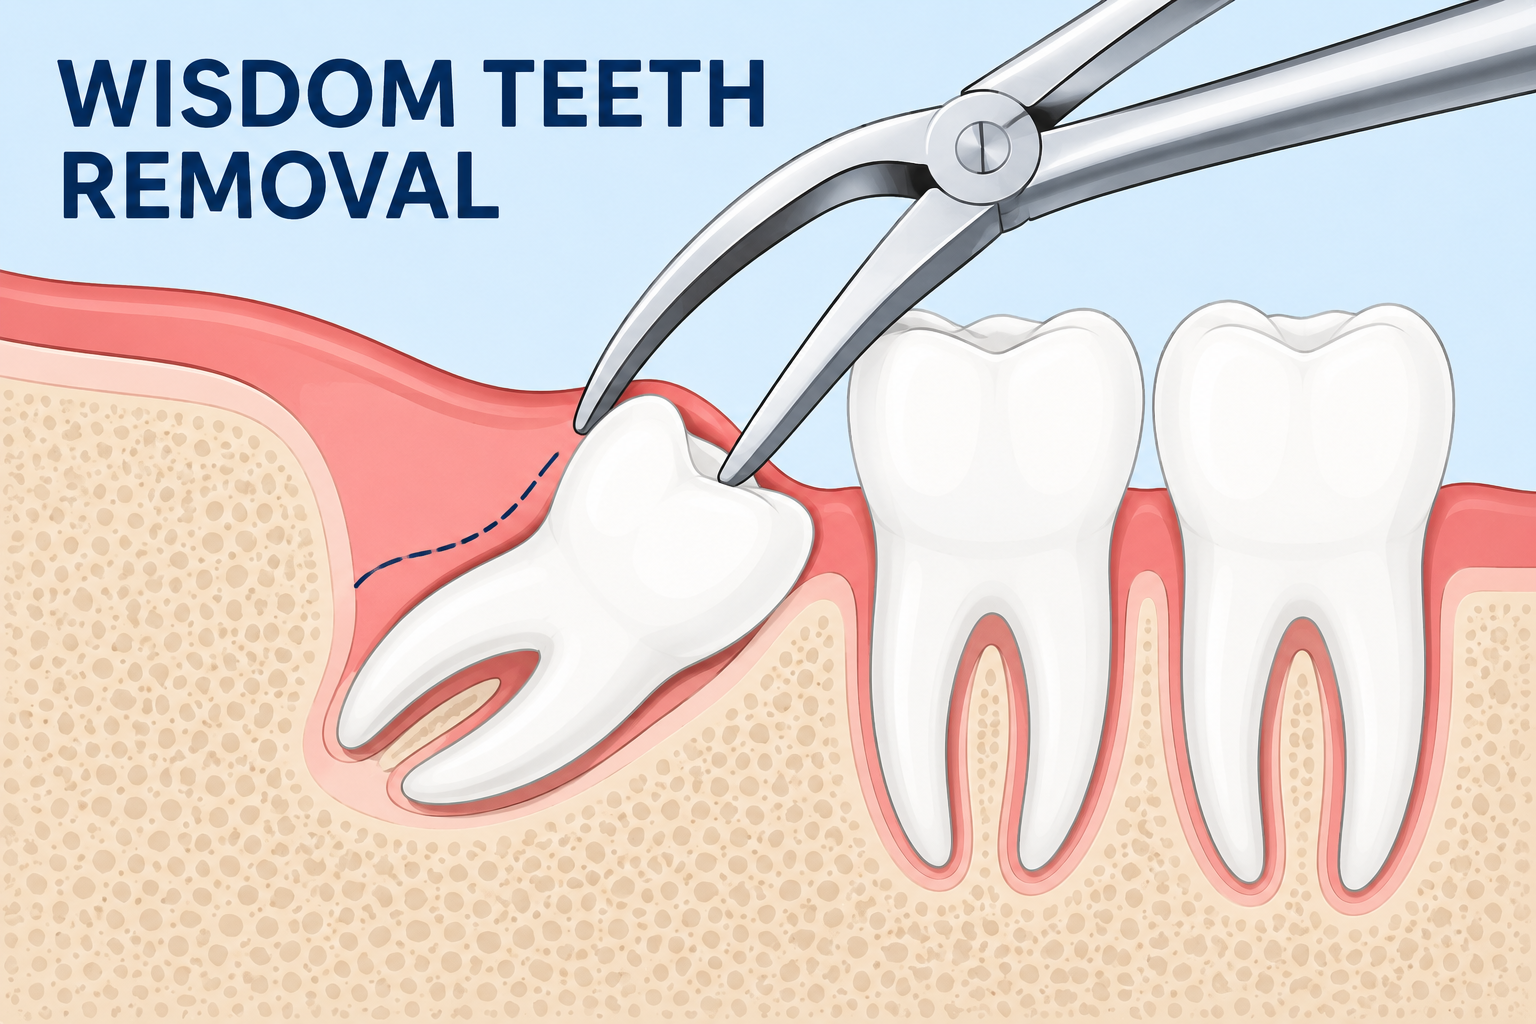

Wisdom teeth removal is a common oral surgery procedure to extract impacted wisdom teeth (third molars) at the back of the mouth. Dentists and oral surgeons recommend wisdom tooth extraction to relieve pain, prevent infection, reduce swelling, and protect nearby teeth from crowding or damage. This safe and effective dental procedure helps maintain long-term oral health and prevents future complications. Learn more →